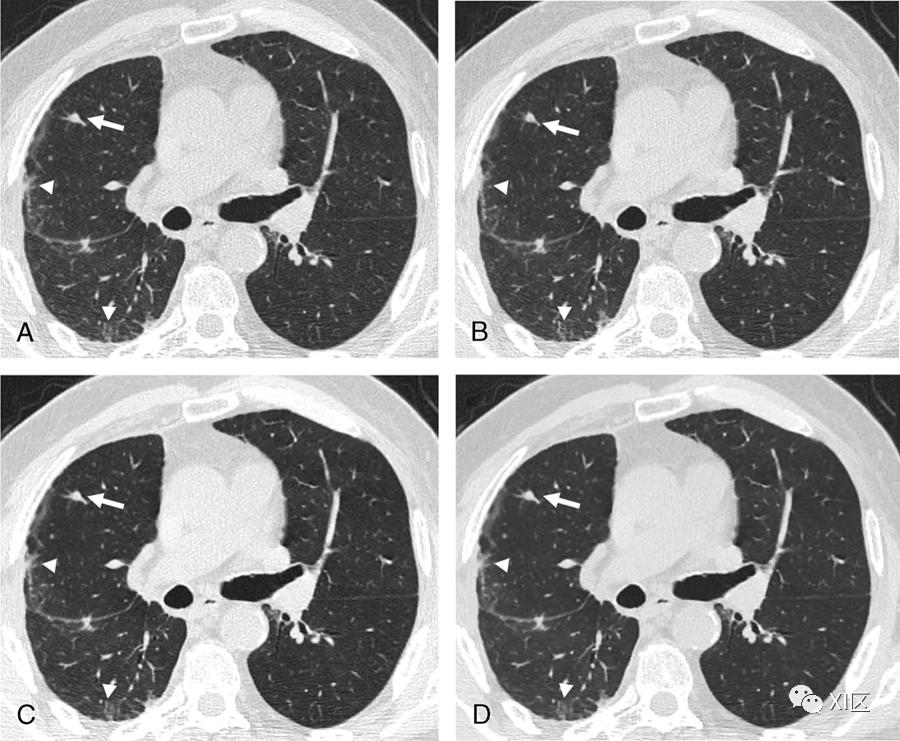

图4 用不同级别的iDose4算法重建的CT图像的比较。一名患有间皮瘤的63岁男子的轴向薄层非增强胸部CT扫描,显示右肺中有一个非钙化的实质结节(白色箭头)和胸膜下结构扭曲(白色箭头)。胸部CT是在100 kVp下采集的,具有管电流调制(mAs范围,109–220)。使用iDose4算法在不同水平重建图像:(A)iDose1、(B)iDoe3、(C)iDos5和(D)iDose7。高强度IR保持高对比度和空间分辨率,为减少辐射剂量铺平了道路。GE医疗